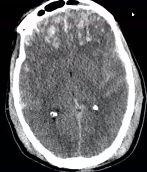

what does this ct show

contusion to the front of the brain

white spots

traumatic subarachnoid are the white streaks in the middle of the brain